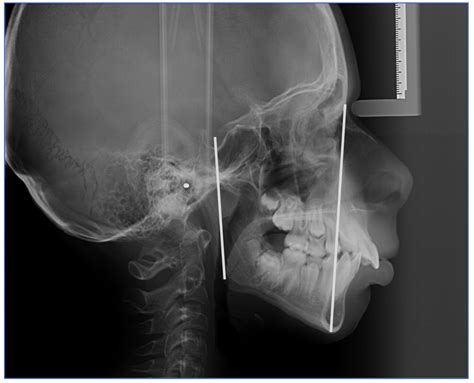

A Cephalometric X Ray is a specialized type of radiograph used to analyze the relationship between the teeth and the jaw. It provides a two-dimensional view of the skull, focusing on the facial bones and teeth. This imaging technique is invaluable for diagnosing and treating various orthodontic conditions, including malocclusions, jaw discrepancies, and facial asymmetries.

The patient’s head is positioned so that the Frankfort plane (a line drawn from the top of the ear canal to the bottom of the eye socket) is parallel to the floor. This ensures that the X-ray beam passes through the skull at the correct angle, providing an accurate image of the facial bones and teeth.

The X-ray machine is then activated, and a beam of radiation is directed through the patient’s head. The radiation passes through the soft tissues and is absorbed by the denser bone structures, creating a detailed image on the X-ray film or digital sensor.